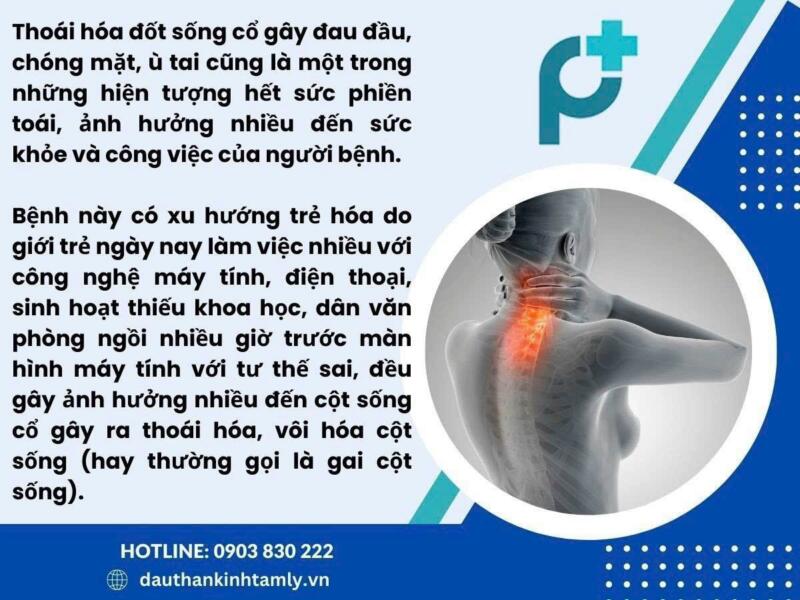

Đau đầu căng cơ và đau cổ gáy do thoái hóa cột sống cổ